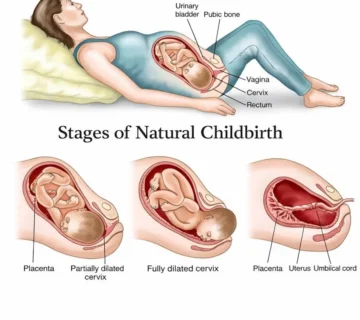

Meanwhile, your uterus is expanding, your belly is becoming rounder, and your breasts may feel larger or more sensitive as your body prepares for breastfeeding.

Your Body in Week 17 of Pregnancy

Your body continues adapting to pregnancy in remarkable ways.

Other Common Body Changes

A growing belly and expanding uterus

Breast tenderness or enlargement

Occasional mild back pain or pelvic pressure